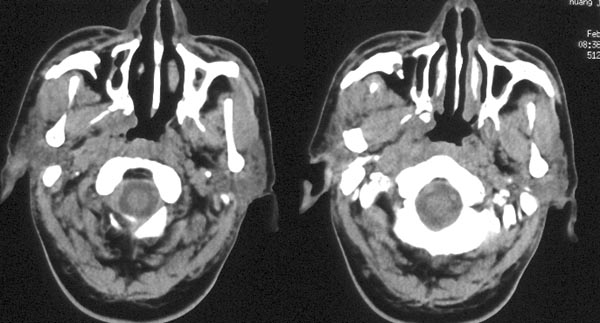

男性,48岁。吸涕带血2月余。

ct平扫:鼻咽腔明显狭窄,鼻咽顶壁、顶后壁、后壁、双侧壁增厚,右侧甚,右侧鼻咽旁间隙、颈动脉间隙见软组织肿物占据,肿物向前达后鼻孔,向下达右侧口咽,肿物向中颅窝侵犯致广泛颅底骨质破坏:包括枕骨斜坡、枕大孔、蝶窦、鞍底、双侧蝶骨大翼、双侧岩尖、双侧翼板。蝶窦、蝶鞍为软组织肿物占据,左侧海绵窦稍增厚。左侧鼻咽旁间隙、颈动脉间隙未见明显异常。

ct诊断:考虑鼻咽癌,并口咽受侵犯、颅底骨质破坏。